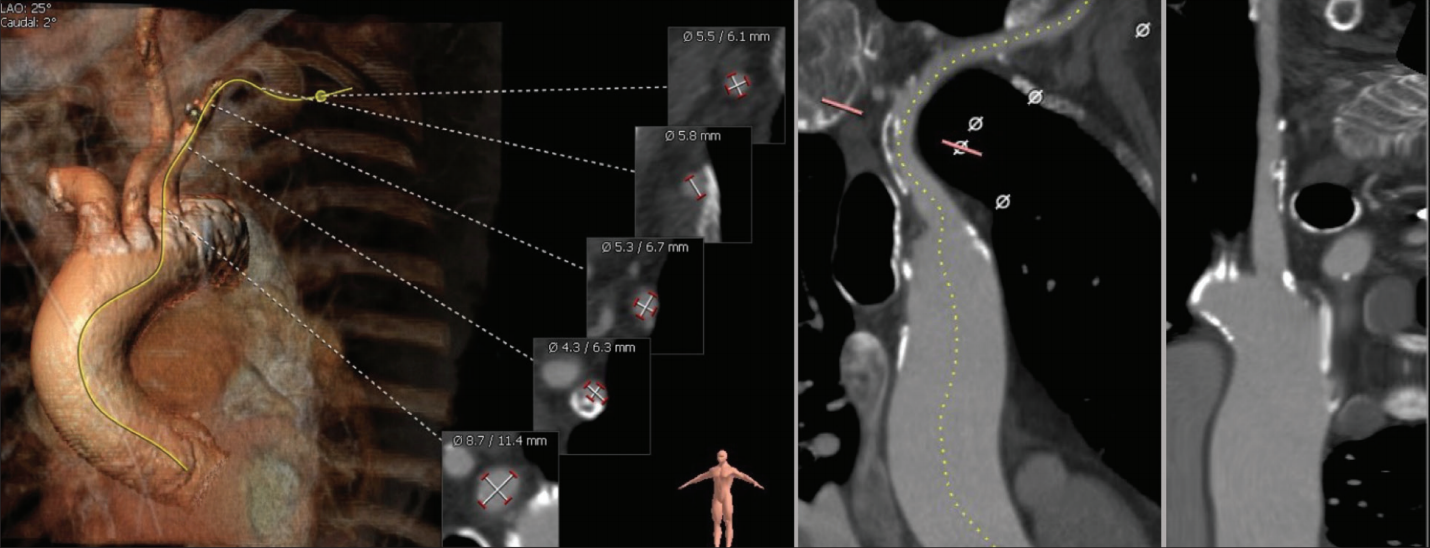

Gated CT demonstrated a trileaflet aortic valve with an annular area of 350.5 mm2, a perimeter of 67.1 mm, and a smallest sinus of Valsalva diameter of 27.5 mm. The aortic annular plane angle was 57° (Figure 3).

The valve team considered that the patient was eligible for TAVR because she had no cognitive impairment, lived alone, and was able to perform her activities of daily living with minimal difficulty. However, because of frailty and advanced chronic lung disease, the CT surgery team considered that the patient was not a candidate for direct aortic or transapical access. Transcaval access was not an option because of extensive abdominal aortic calcification. Further CT analysis demonstrated that the right subclavian and innominate arteries were large enough, with a minimum diameter > 5.5 mm. Based on the experience with previous vessel navigation during cardiac catheterization demonstrating that the tortuous subclavian anatomy would be easily straightened, the patient underwent transaxillary TAVR with surgical cutdown, general anesthesia, and a 23-mm Sapien 3 transcatheter heart valve. Even though transseptal antegrade access was an option for this patient, we opted for transaxillary access because of her small left ventricular cavity with hypertrophy (Figure 3) and lower procedural risks. The patient went home a week after the procedure.